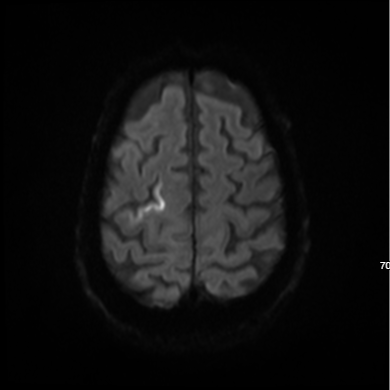

Brad Oliverson, D.O., was the emergency physician on shift and contacted David Wheeler, M.D., the on-call neurologist and medical director of Banner Wyoming Medical Center’s stroke program. Dr. Wheeler ordered an immediate stroke protocol CT scan to detect the amount of blood flowing into Ron’s brain as well as show the specific anatomy of his arteries. The hospital also administered intravenous tPA – or tissue plasminogen activator, a protein used to break apart blood clots and, hopefully, restore blood flow to the brain.

Then Ron was flighted to Banner Wyoming Medical Center.  When he arrived, Dr. Wheeler along with interventional radiologist Eric Cubin, M.D., determined that Ron’s stroke was not yet complete and that he was a good candidate for mechanical clot retrieval. Interventional radiologists make this type of stroke treatment possible at Banner Wyoming Medical Center.  Fellow interventional radiologist Ryan Bonifield, D.O., came over to perform the procedure.

Fortunately for Ron, Banner Wyoming Medical Center’s multidisciplinary team is experienced in springing into action for severe strokes such as the one he suffered. Inside the interventional radiology suite, Dr. Bonifield accessed the common femoral artery near Ron’s groin and inserted a small guide wire covered with a vascular sheath. Guided by real-time X-ray imaging, Dr. Bonifield snaked the guide wire through Ron’s arteries and around a complex path to the artery in his neck. He then passed smaller tubes into the blocked artery in Ron’s brain and released a special device to grab the clot and remove it. After three passes, he retrieved the clot and restored blood flow to Ron’s brain.